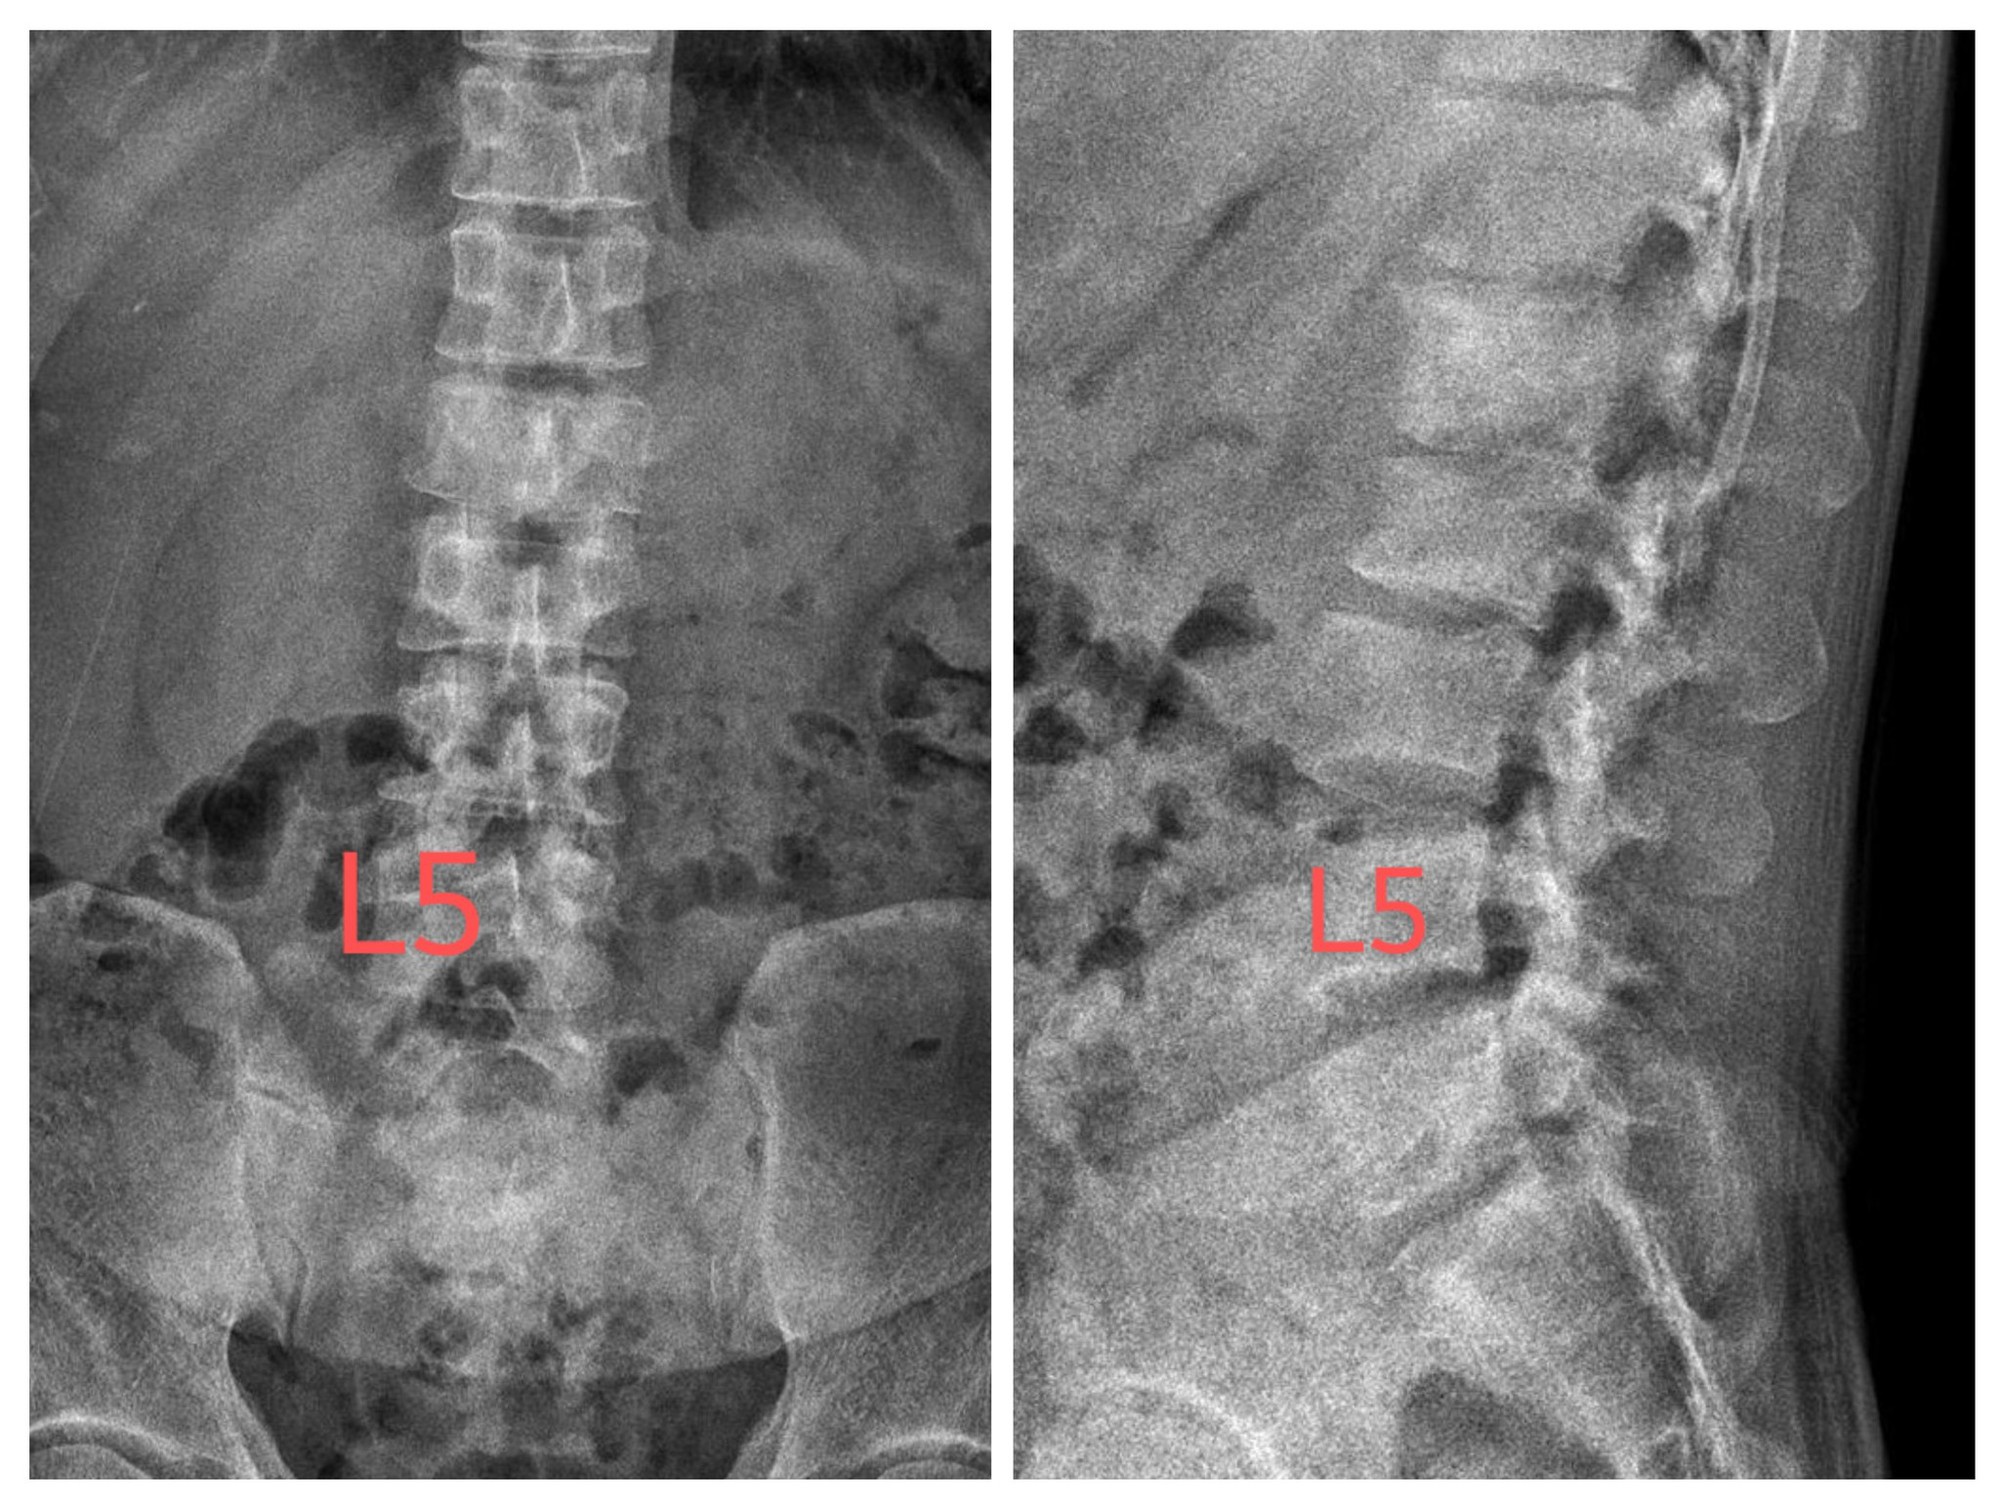

Sau khi xem xét kỹ lượng hình ảnh ở cả phim chụp trước - sau và phim chụp nghiêng, BS Cao Thanh Phong cho biết hình ảnh xuất hiện dấu hiệu "mắt cú mèo", hủy 2 bên cuống sống. Đây là dấu hiệu ung thư xương và thường gặp khi bệnh tiến triển nặng.

Bệnh nhân bị ung thư xương di căn khi mới 26 tuổi.

Sau khi đánh giá hình ảnh ban đầu, BS Phong khuyến cáo bệnh nhân đến bệnh viện tuyến đầu để chụp CT và MRI có tiêm thuốc đối quang từ. Việc phân loại tổn thương, đánh giá mức độ tiến triển và điều trị cần để bác sĩ chuyên khoa đảm nhiệm.

Theo BS Phong, dấu hiệu "mắt cú mèo" là hình ảnh điển hình của ung thư di căn xương. Hủy cuống sống thường là tổn thương thứ phát nhưng không thể loại trừ nguyên phát. Dấu hiệu này dễ bị bỏ sót vì mọi người thường chủ quan do nghĩ đây là đau lưng và đau ngực đơn thuần hoặc nhầm lẫn với các bệnh lý khác, chỉ vô tình được phát hiện khi chụp phim X-quang.